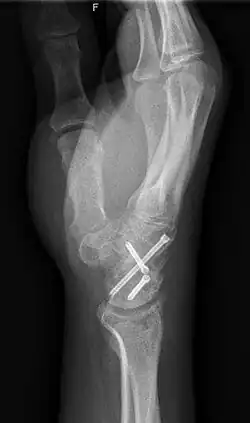

Arthrodesis is the surgical immobilization of bones within a joint to promote fusion of the joint.[20] Arthrodesis is performed most commonly on joints of the feet, hands, and spine.[21][22][23] Arthrodesis can relieve pain from arthritis and fractures.[24] This is accomplished through the use of orthobiologics such as allografts and autografts.[25] Allografts are done by creating bone grafts from a donor bone bank, whereas autografts are bone grafts from other bones in a patient's body.[25] Patient-reported outcomes following this procedure are typically positive in terms of long-term pain relief; however, the procedure also results in decreased range of motion.[26]

Arthroplasty, otherwise known as joint replacement, is a surgical procedure which involves resurfacing, realignment, or removal of bone at a joint interface to restore the joint's function.[27] Arthroplasty is often performed on hips, knees, shoulders, and ankles to improve range of motion and relieve pain from arthritis or trauma.[28][29] Arthroplasty of the shoulder is one of the most common of these procedures, although it has only been widely used since 1955.[30] Themistocles Gluck is thought to have created the first shoulder arthroplasty in the 1800s.[30] Since Gluck never published any results or notes on the procedure, Jules-Emile Pean is credited with performing the first shoulder arthroplasty in 1893.[30]